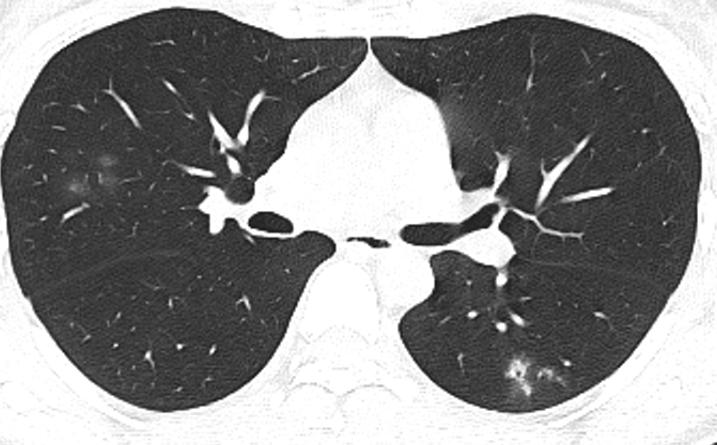

胸部CT示:双肺多发磨玻璃结节,左下叶背段散在实性结节,散在小空洞,部分支气管的管壁增厚,如下(图1~17)。